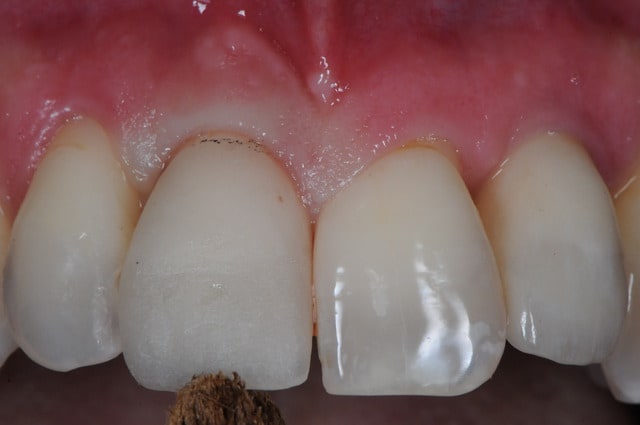

Vous tenteriez l'EII dans ce cas ci

Il y a 3.6 mm d'os au dessus du granulome

pas que pour le granulome...d'ailleurs...mais aussi parce que tu as une belle fracture vestibulaire qui fait que la corticale...bein y en a plus...ou quasi plus...